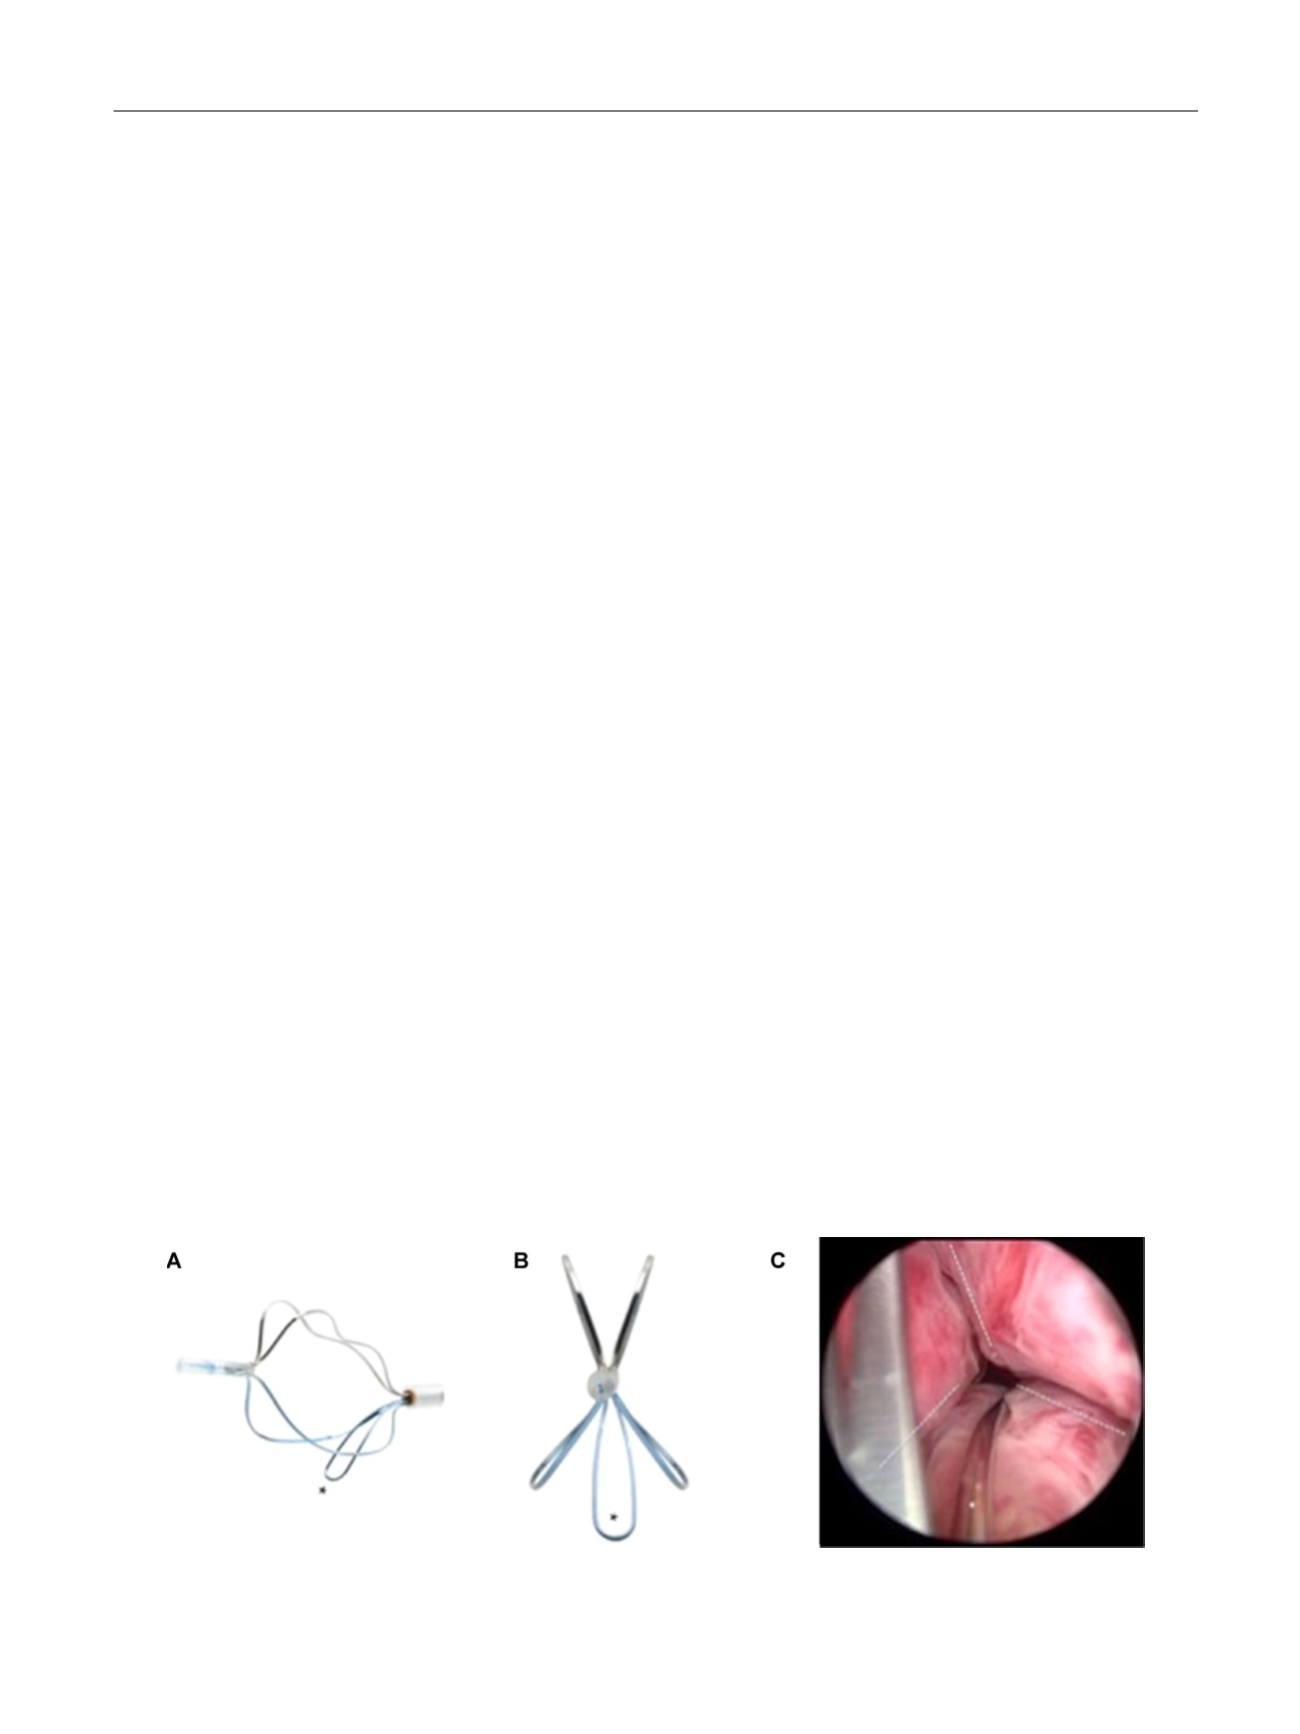

TIND (Medi-Tate; Medi-Tate Ltd., Or Akiva, Israel) is an

emerging device designed to remodel the bladder neck and

the prostatic urethra in an unprecedented way

( Fig. 1). The

TIND is composed of elongated struts and an anchoring

leaflet, all made of nitinol. Under cystoscopic guidance the

device is preloaded on a dedicated delivery system and

advanced through a standard 22-F cystoscope sheath in an

up-folded configuration. The dimensions of this tool (total

length: 50 mm, outer diameter: 33 mm) were designed to

cover the complete prostatic urethra, ranging from bladder

neck to proximal to the external urinary sphincter. Under

direct visualisation the TIND is deployed inside the bladder

in expanded configuration. Anchoring the leaflet slide at the

6 o’clock position distal to the bladder neck ensures precise

and safe positioning within the bladder neck and the

prostatic urethral lumen. The intended mode of action is to

compress obstructive tissue by the expanded device, whose

struts will exert radial force leading to ischaemic necrosis in

defined areas of interest. The TIND is left in position for 5 d,

time enough to create prostatic incisions anteriorly, at the

5 o’clock and 7 o’clock positions. The resulting incisions may

be similar to a Turner Warwick incision. In an outpatient

setting the device is safely removed by standard urethro-

scopy.

[(Fig._1)TD$FIG]

Fig. 1 – Temporary implantable nitinol device (TIND). (A) TIND in its expanded configuration, longitudinal view. (B) TIND in its expanded configuration,

front view. (C) Cystoscopic visualisation: the anchoring leaflet is in its correct position (*) and the incisions are visible (—). Length: 50 mm, width:

33 mm.